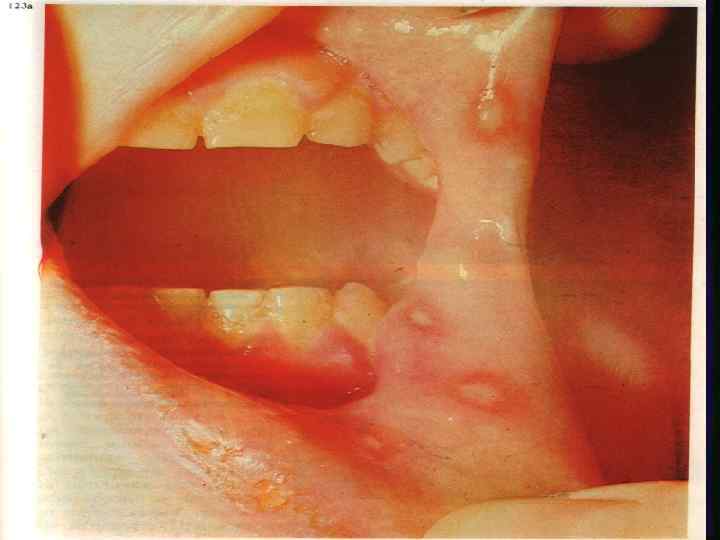

ЯЗВЕННО НЕКРОТИЧЕСКИЙ ГИНГИВО СТОМАТИТ ВЕНСАНА ДИАГНОСТИКА ЯЗВЕННО НЕКРОТИЧЕСКОГО ГИНГИВО СТОМАТИТА ВЕНСАНА